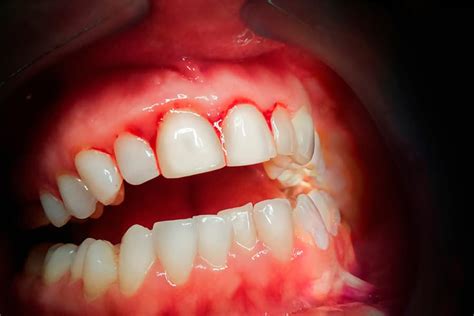

El sangrado de las encías es un síntoma que indica que algo no está bien en nuestra salud bucal. Aunque un ligero sangrado ocasional puede no ser motivo de gran preocupación, un sangrado persistente y abundante requiere atención y cuidado. A continuación, exploraremos las causas reales del sangrado de las encías y las soluciones efectivas para prevenirlo y tratarlo.

Las encías sangrantes son un signo de inflamación en las encías, conocido como gingivitis. En la mayoría de los casos, el sangrado de las encías se debe a una gingivitis o a una lesión en la boca.

- Gingivitis: La gingivitis es una enfermedad periodontal que cursa con inflamación de las encías y sangrado que, con el adecuado tratamiento, puede revertir. Esta enfermedad periodontal produce una inflamación de las encías y Suele suceder por la acumulación de placa bacteriana entre los dientes.

El sangrado de las encías no es una enfermedad en sí, sino un síntoma. Lo cierto es que las encías sanas no sangran, por lo que nunca debes tomarte el sangrado de encías a la ligera. Puede ser inofensivo y desaparecer por sí solo con un cuidado bucal adecuado. Sin embargo, también puede ser un signo de una enfermedad más grave, como la periodontitis o incluso la leucemia.